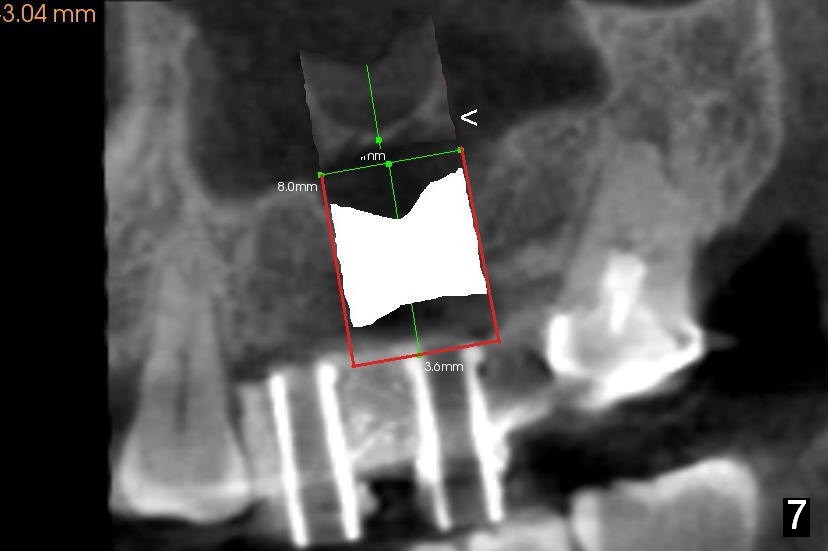

After crestal incision, a 3.5 or 4 mm trephine bur is used for 2 mm at #14. The regional sinus floor is lifted using a Bicon flat-end osteotome, followed by bone graft and taps. If the 6x11 mm tapered tap does not gain stability (Fig.3), use either 6x11 mm round tap (Fig.4) or 7 or 8x11 mm tapered tap (Fig.5). If the last does not work, try a larger round tap (Fig.6). In all, the sinus floor is pushed upstairs and an implant is inserted to be engaged into the sides of the sinus floor (Fig.7).

Coronally, a round implant does not appear to obtain more bone contact than a tapered one of the same diameter (Fig.8,10). Internal sinus lift works for this case?